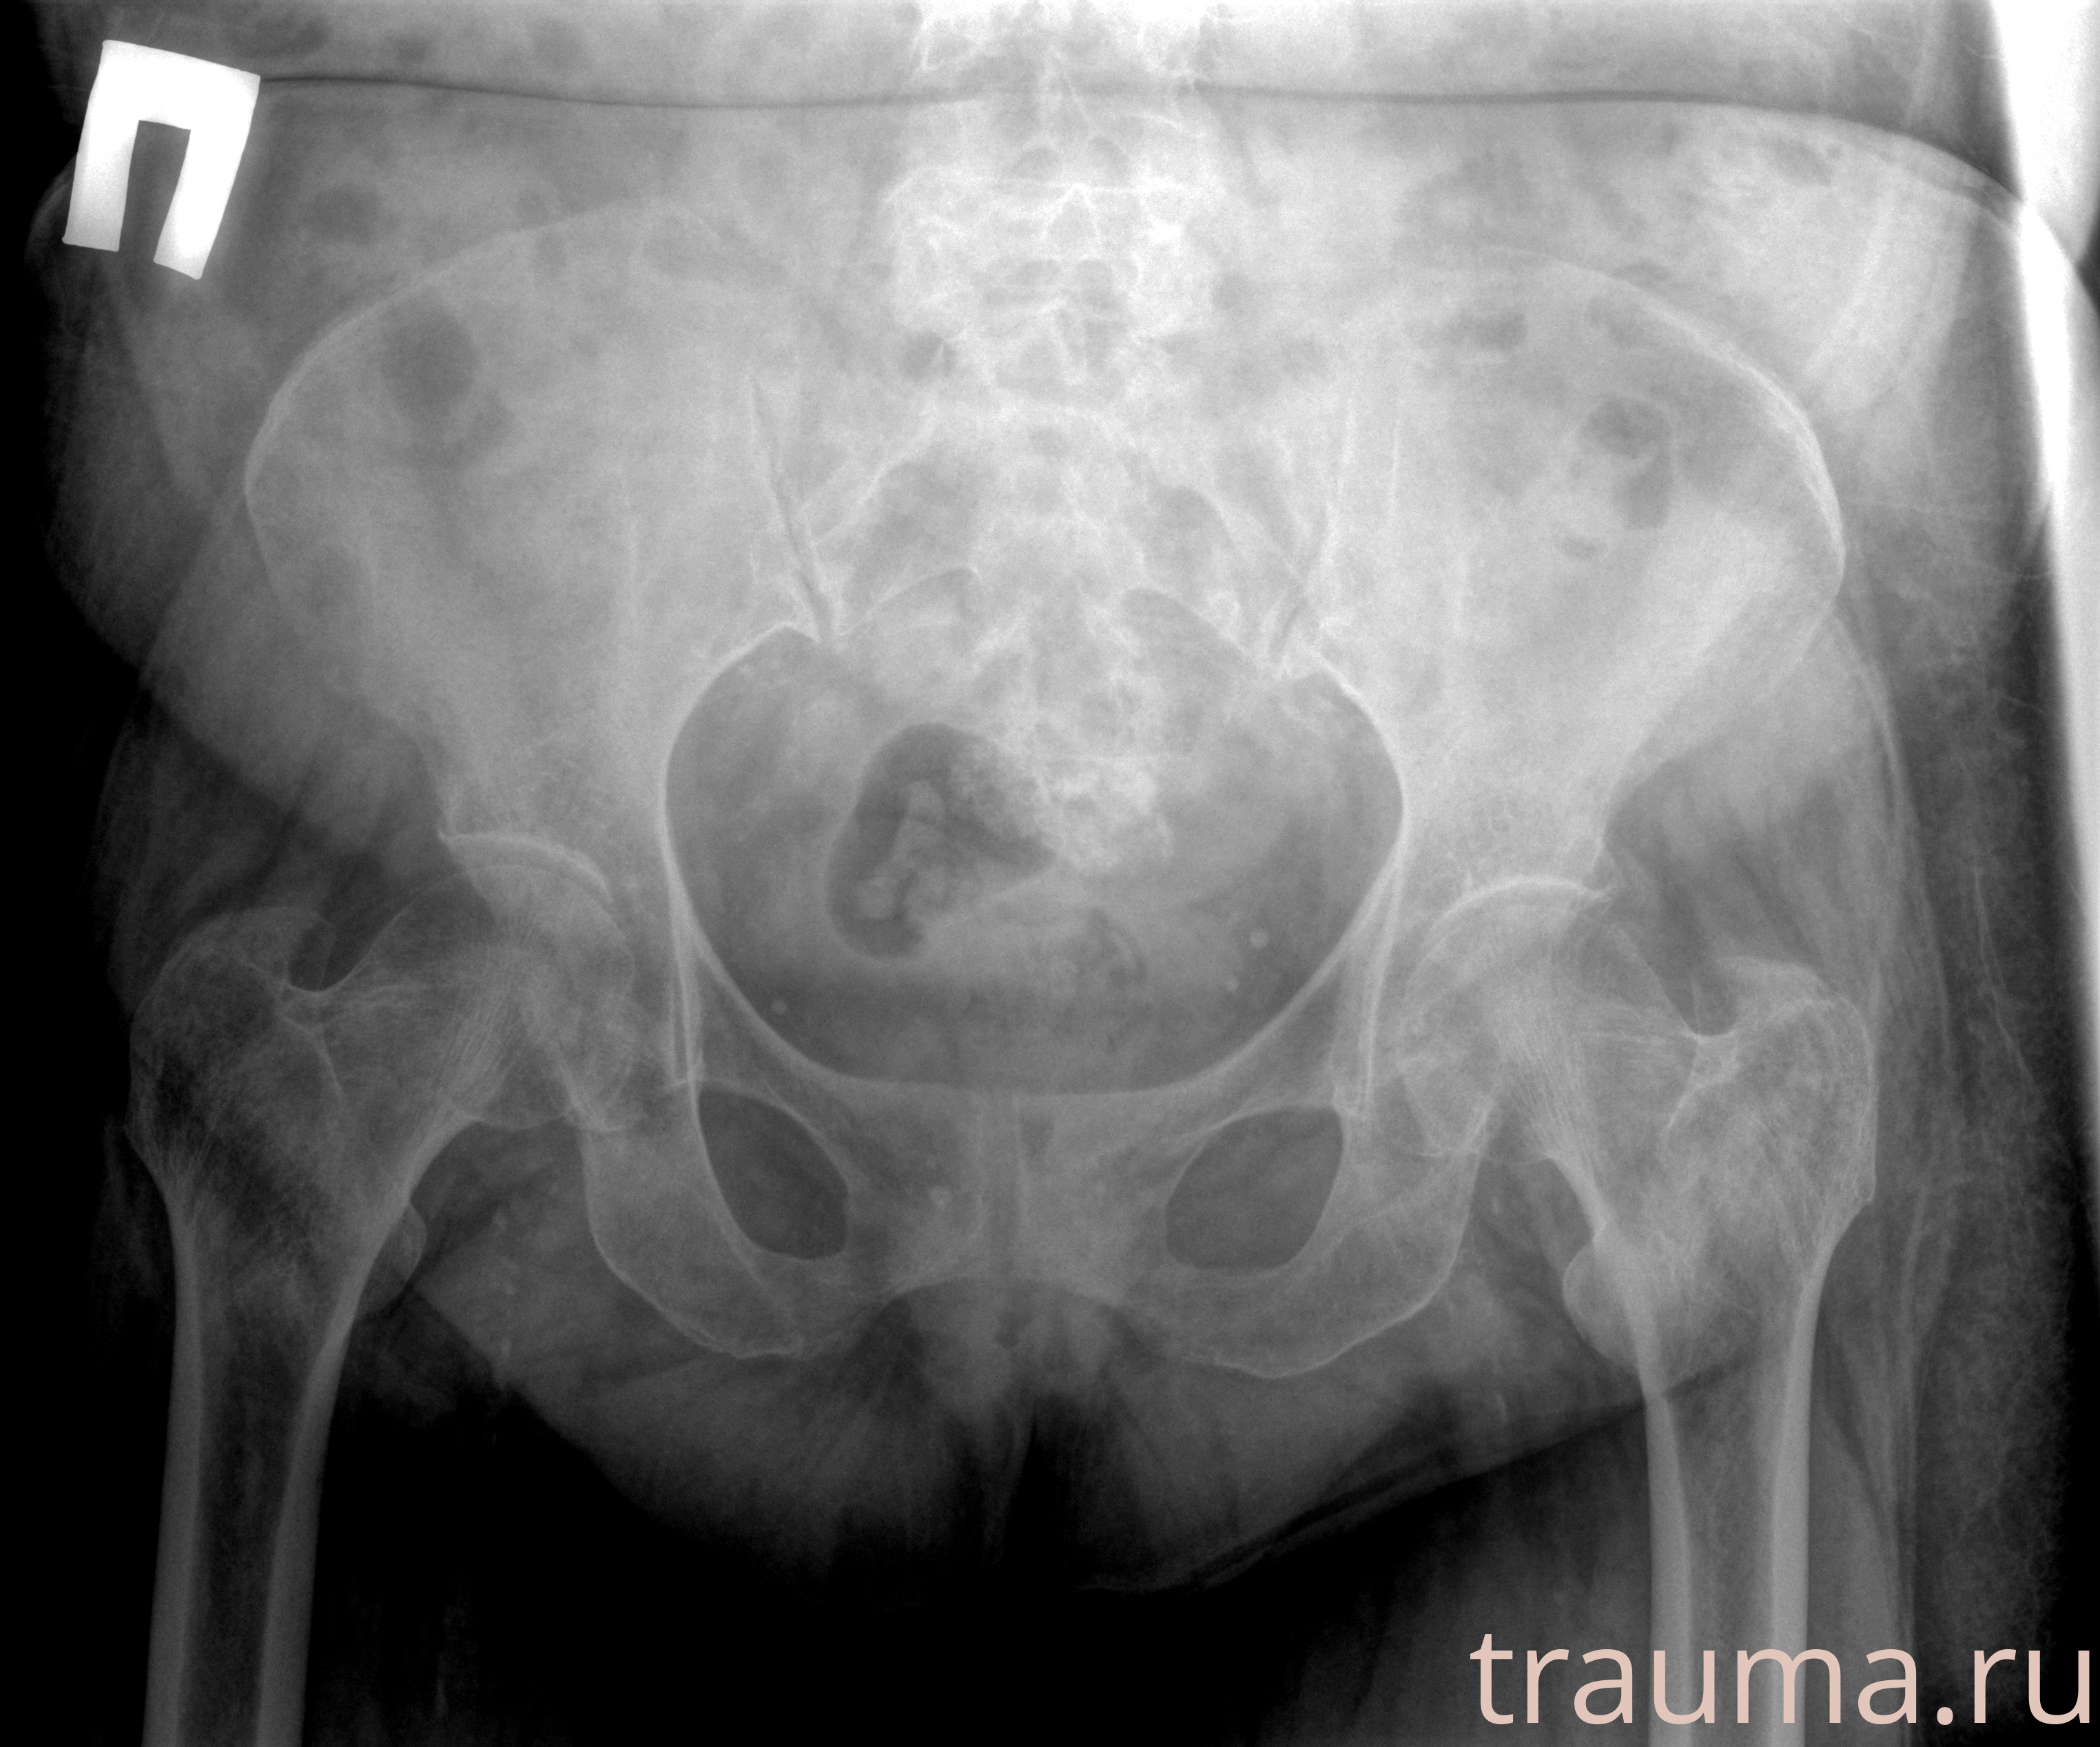

Рентгенограммы

Рентген на дому: по вашему адресу приезжает врач-рентгенолог, травматолог-ортопед с мобильным рентгеновским аппаратом, проводит диагностику травмы или заболевания, делает необходимые рентгенограммы, дает рекомендации по дальнейшему лечению. Получить качественные снимки в домашних условиях возможно благодаря уникальной методике, разработанной МосРентген Центром для института  Склифосовского

при переломе шейки бедра и пневмонии от компании МосРентген Центр - партнера Института имени Склифосовского